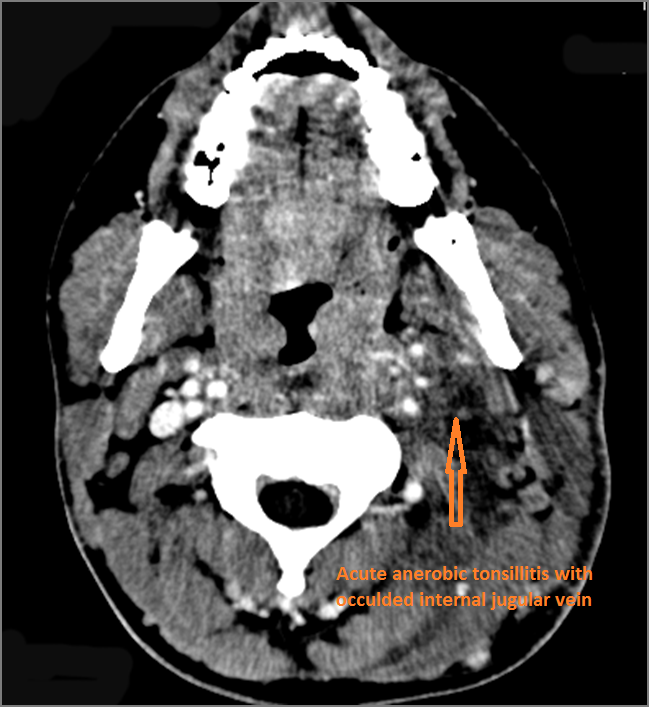

There is excessive enhancement or thickening of the mucosa or hypertrophy of the palatine or lingual tonsillar tissue or the lymphoid tissue along the glossotonsillar sulci and posterior pharyngeal wall. [Yes/No]

There is abscess relatively centrally within the lymphoid tissue of the palatine tonsil. [Yes/No]

There is evidence of thrombus, thrombophlebitis or other occlusive or inflammatory process of the jugular vein. [Yes/No]